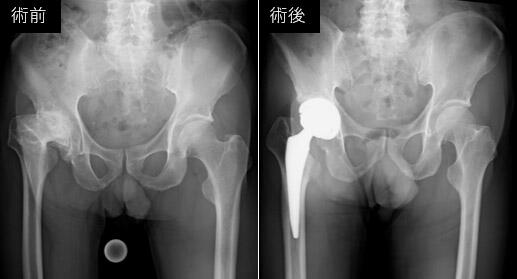

整形外科では、コンピューター支援技術を積極的に活用し、安全性が高く、低侵襲かつ高精度な人工股関節置換術や人工膝関節置換術を実施しています。特に、当院独自に開発した拡張現実(Augmented Reality, AR)技術を取り入れたナビゲーションシステムを導入することで、より正確な手術を実現しています。この技術により、血管や筋肉を詳細に描出することが可能となり、さらなる安全性の向上に貢献しています。また、ロボット支援手術も取り入れており、これら最先端のデジタル技術によって、精密で個別化された医療を提供し、治療成績の向上を目指しています。基礎研究においては、変形性関節症や関節リウマチの病態解明、関節軟骨の修復・変性抑制など、幅広いテーマに取り組み、次世代の医療技術の開発に努めています。